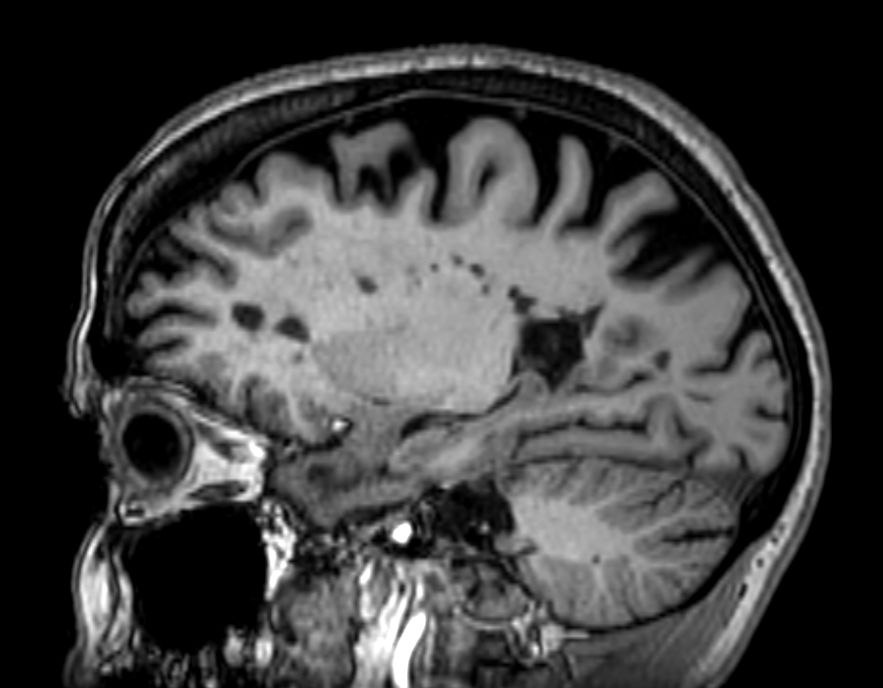

3D Double IR BrainVIEW (reformat) Compressed SENSE

3D Double IR BrainVIEW Compressed SENSE